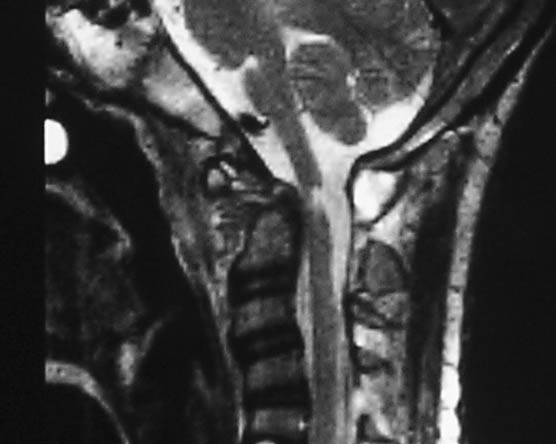

Spinal Tuberculosis

Tuberculosis of spine is the commonest form of the disease after the one involving the lungs. Pain over the spine and back is the initial symptom, followed by weakness of the limbs due to compression of the spinal cord due to formation of pus and collapse of spine. Complete evaluation by MRI, followed by surgery at appropriate level results in rapid recovery and early return ot work. Surgery may have to be accompanied by insertion of spinal implants to achieve stability and pain free back. Complete course of antituberculous drugs is mandatory for cure.